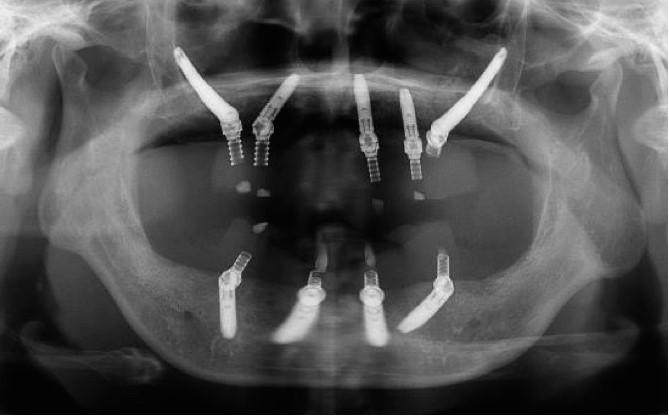

手術(shù)當(dāng)天,江宏兵院長在數(shù)字化外科導(dǎo)板和數(shù)字化導(dǎo)航輔助下,于上頜后牙區(qū)成功植入2枚Nobel穿顴種植體,前牙區(qū)植入3枚NobelParallel CC種植體,并在上頜竇開窗區(qū)及過薄的種植體唇側(cè)充填骨粉,覆蓋膠原膜。下頜則在數(shù)字化外科導(dǎo)板引導(dǎo)下,避開患者數(shù)年前充填的美容假體和其他重要解剖結(jié)構(gòu),植入4枚NobelParallel CC種植體,所有種植體初期穩(wěn)定性均達(dá)到35 N?cm,符合負(fù)重的要求。

按照術(shù)前計劃于上下頜植入共9枚種植體